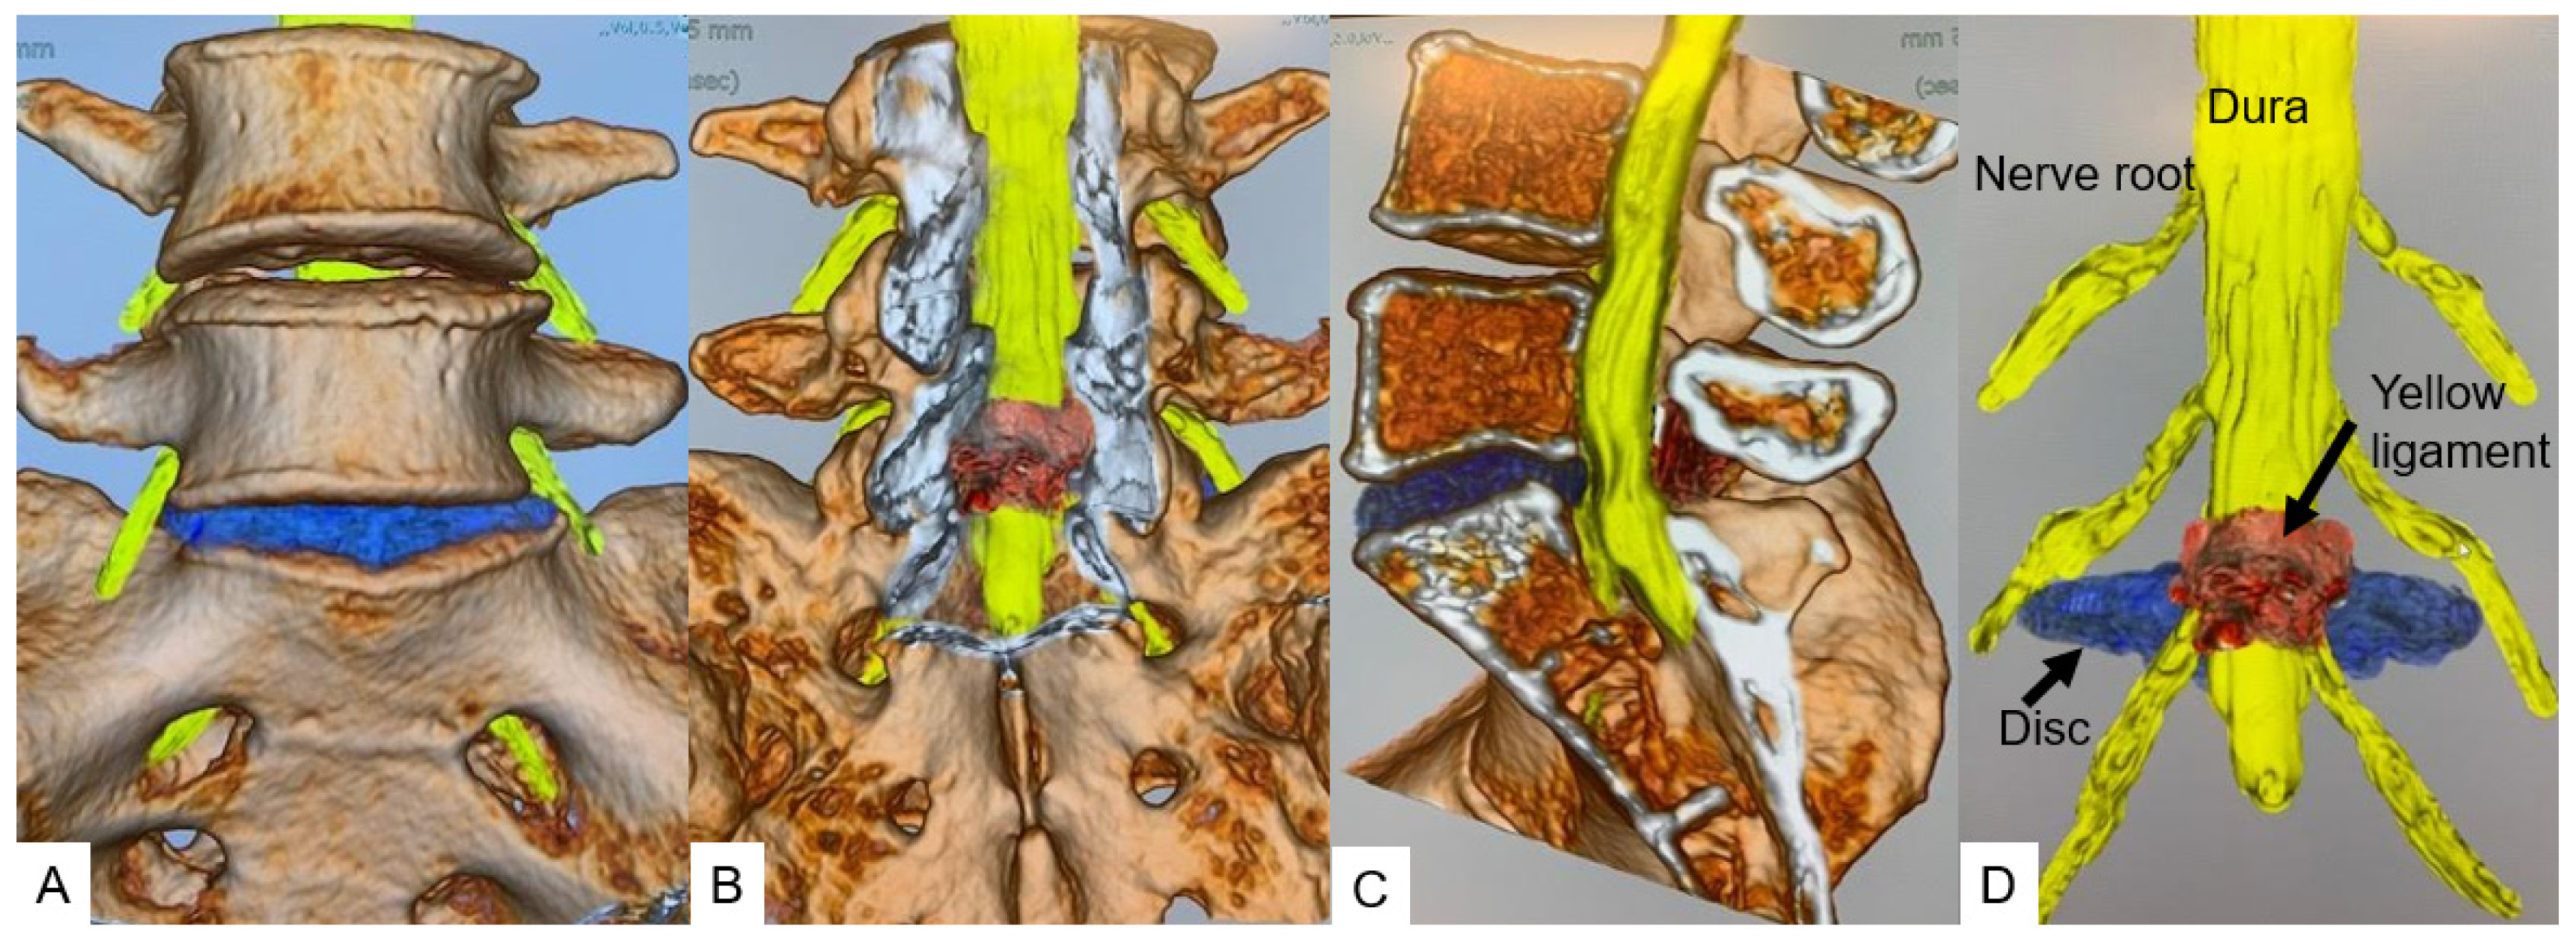

All herniated discs were visualized in the fusion images, and the root compression site was clearly demonstrated in foraminal/extraforaminal disc herniations (Figure 6, Figure 7 and Figure 8).

Figure 6.

A 46-year-old male, left L5/S1 foraminal/extraforaminal disc herniation. (A): Anterior view. (B): Posterior view. (C): Lateral view. (D): Without bony structure.

Figure 7.

A 46-year-old male, left L5/S1 foraminal/extraforaminal disc herniation. (A): Anterior view. (B): Lateral view. (C): Anterior oblique view. (D): Posterior oblique view.

Figure 8.

A 44-year-old female, right L2/3 paramedial disc herniation. (A): T2 weighted midsagittal MRI. (B): L2/3 T2 weighted axial MRI, (C): Posterior view. (D): Without bony structure.